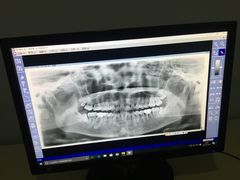

• 德伦口腔

• -德伦口腔

王群_5733 | 17-12-09

报错